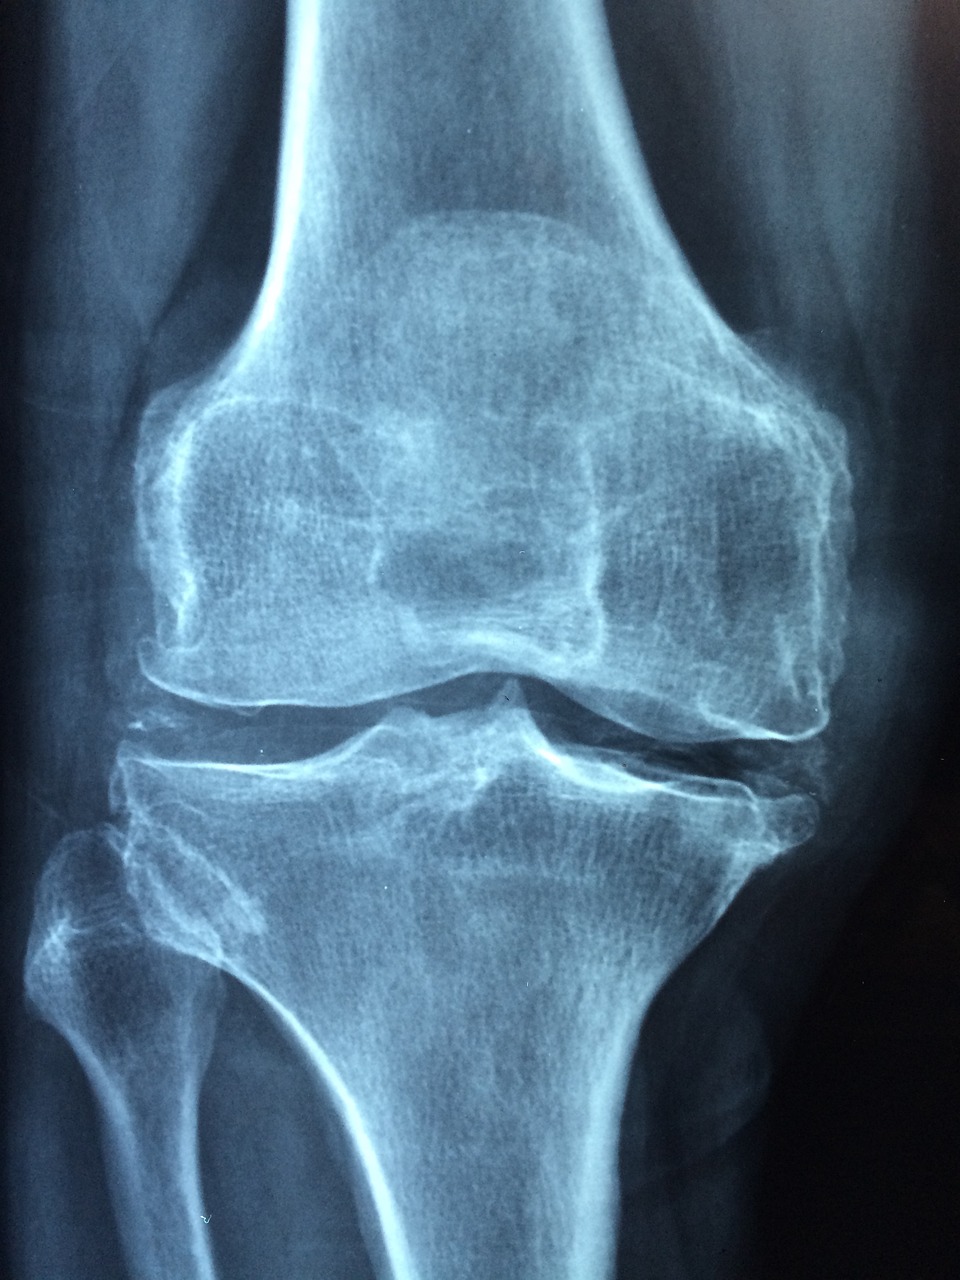

골다공증 검사는 뼈의 밀도와 강도를 평가하여 골절 위험을 판단하는 데 사용됩니다. 주요 검사 방법은 골밀도 검사로, DXA(이중 에너지 X선 흡수계측법)가 가장 널리 쓰입니다.

DXA는 척추와 대퇴골의 뼈 밀도를 측정하여 골다공증 여부를 판단합니다.

- 주요 측정 부위: 척추, 대퇴골, 손목 등이 일반적입니다.